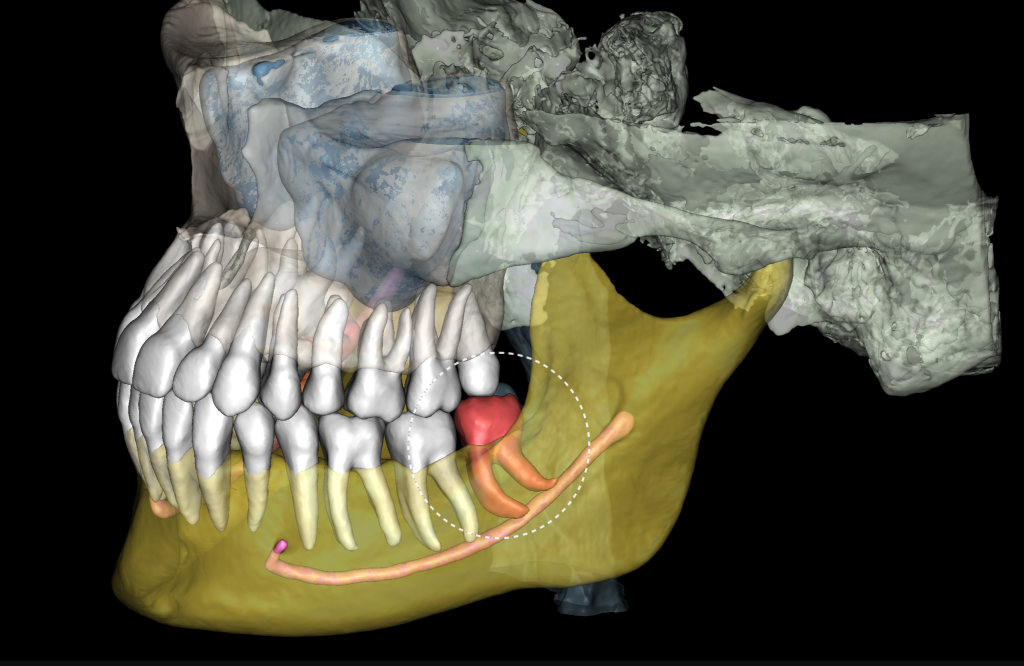

The 3D reconstruction from CBCT data (STL report Diagnocat) is a convenient tool for determining the level of complexity of the upcoming surgical procedure

It also serves as a visualization tool during communication with the patient

“Third Molar Report” created by Diagnocat AI, is a tool which provides accurate tracing of the mandibular canal

And creating an optimal 3D visualization which helps the clinician to determine the distance to the mandibular canal